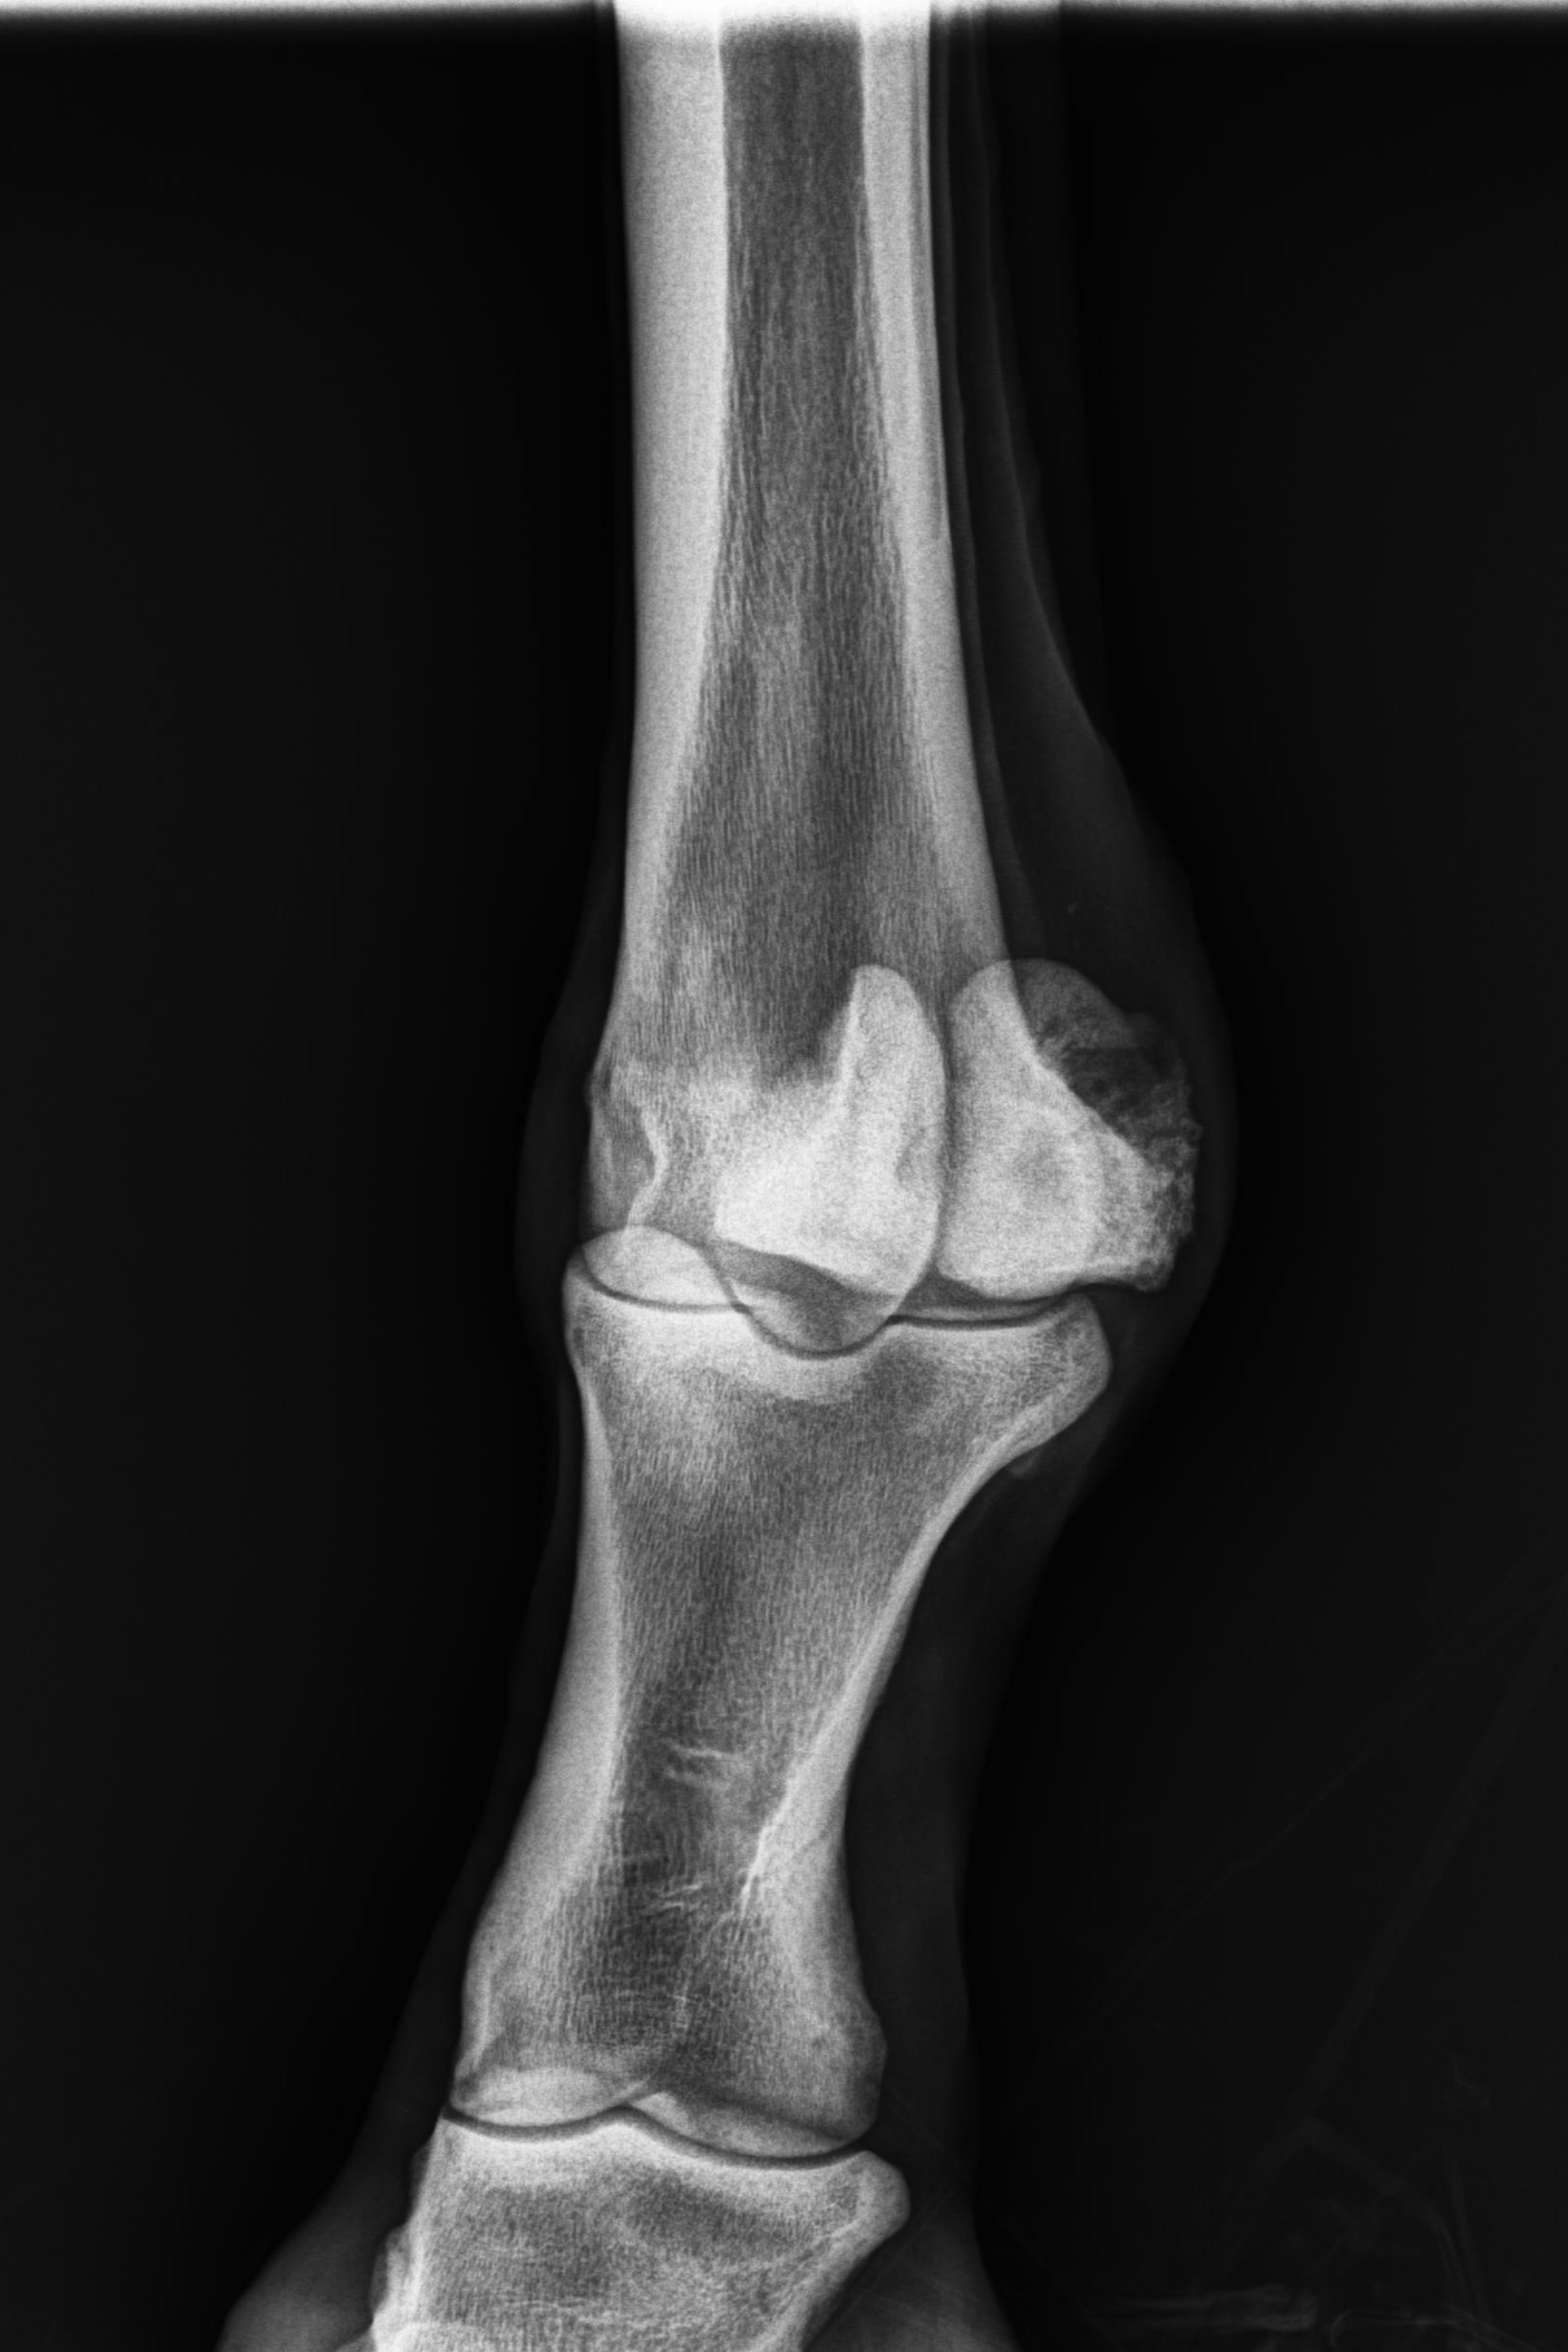

そんな状況の中、1月9日にレントゲン検査を受けると「左前肢外側の種子骨のボーンシスト」が原因と判明しましたので、サラブレッドオークションへ出品とさせていただきます。現状のままでは競走馬としてのデビューは難しいかも知れません。皆様には現状をご理解いただき、事前に獣医検査を受ける等、ご納得をいただいた上でのご検討、ご入札をお願いし、現状渡しのノークレーム、ノーリターンでお願いいたします。

セールの後からお預かりして来ましたが、レントゲン検査を受けて獣医から「このまま調教を進めたら骨折するリスクが大きい」との所見でした。競走馬は勿論ですが、現状のままでは乗馬としても厳しいと思います。(Team百馬力・原翼氏)